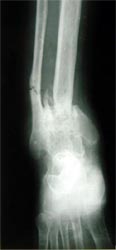

病例三、患者男性,25岁,胫骨下段骨不连3年

图3 病例三、患者男性,25岁,胫骨下段骨不连3年。我们用异体骨板提供支撑力,植如患者自体骨髓细胞经与松质骨和骨生长因子复合物,骨折在9个月后愈合。